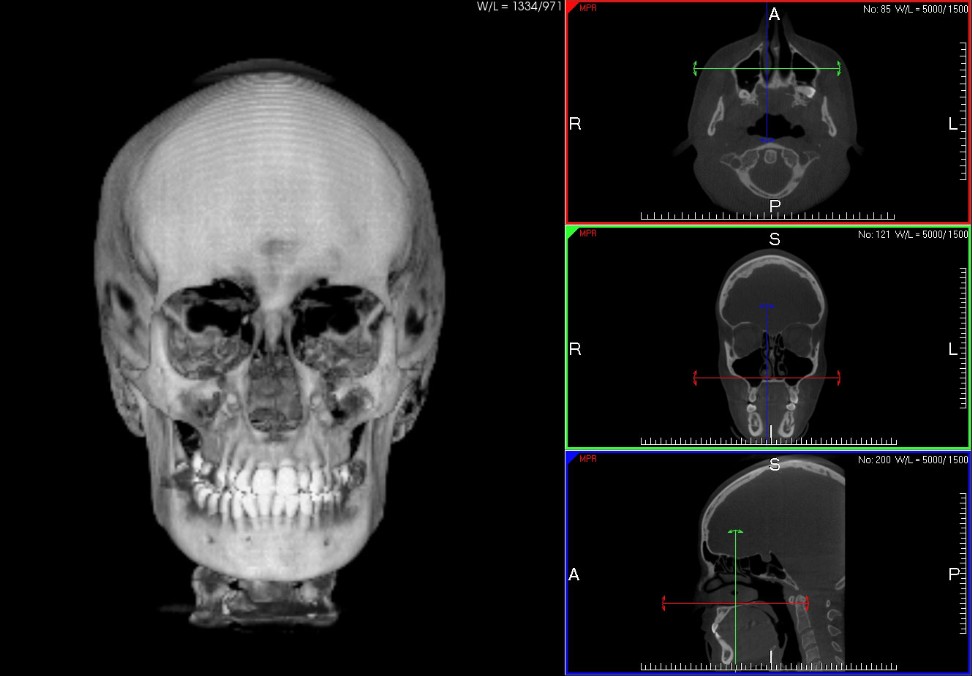

• C.T. Cranio intero Per Ortodonzia

C.T. Cone Beam

La C.T. Cone Beam (CTCB) o anche TAC Cone Beam è una TAC a Basso Dosaggio utilizzata per la diagnosi delle patologie dell’Apparato Masticatorio, del distretto Maxillo-Mandibolare e nell’ ambito Otorinolaringoiatrico; la C.T. Cone Beam ha sostituito l’utilizzo della TAC Multislide (Medical) in Odontostomatologia poichè evidenzia delle immagini con migliore definizione e con  una dose radiogena al paziente 20 volte inferiore.

La C.T. Cone Beam può efettuare scansioni di volume diverso a secondo della necessità con una definizione di immagine diversa (più Piccolo è il Volume Maggiore è la Definizione dell’Immagine):

14 cm diametro X 24 Cm haltezza, per una indagine del Cranio Intero